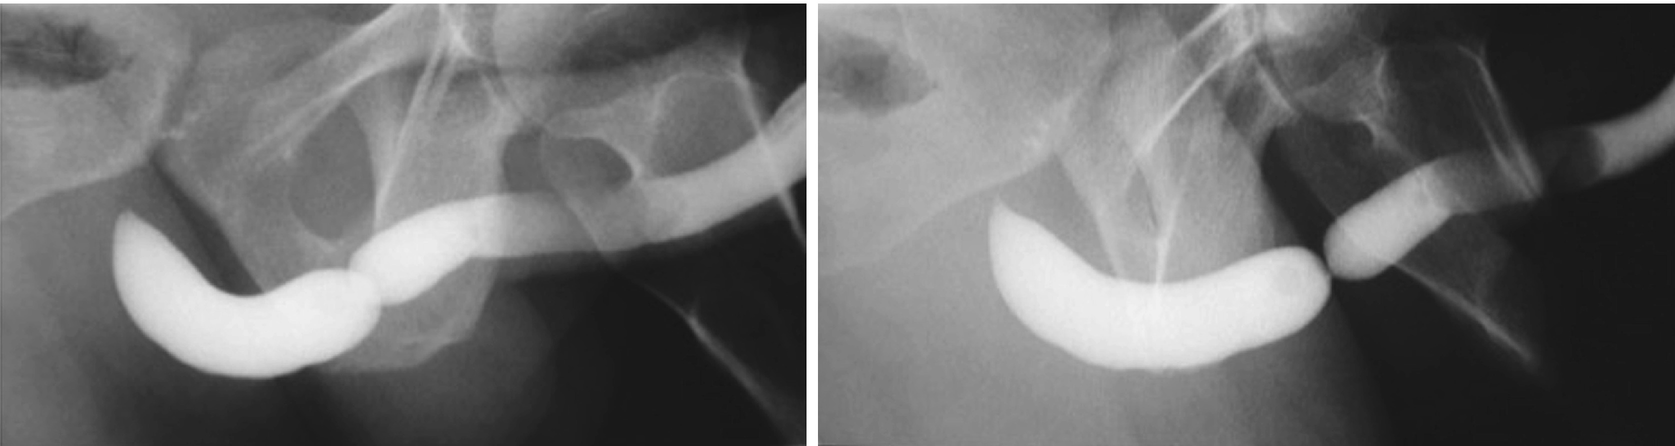

5.3.2 Retrograde Urethrogram and Voiding Cystourethrogram

These two urethrograms on the same patient without and with proper oblique positioning demonstrate the importance of proper positioning during urethrogram. Without a sufficient oblique positioning the presence and length of stricture can be underestimated